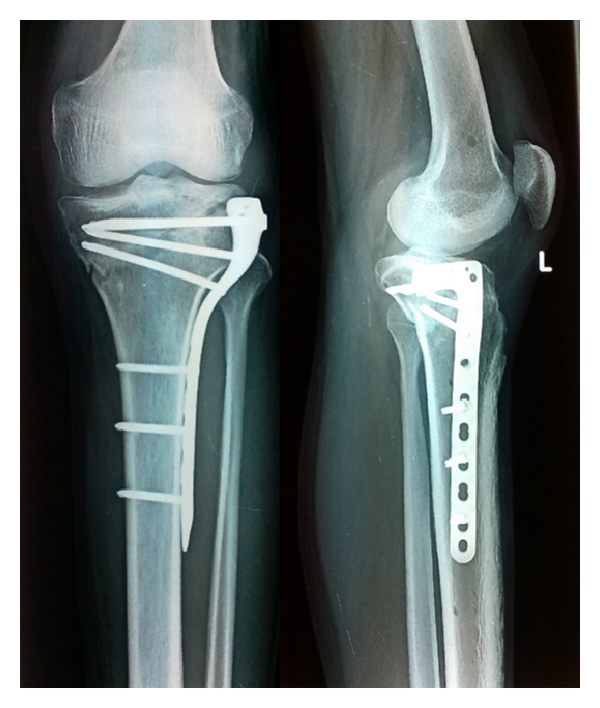

最常见的就是钢板 , 比如胳膊骨折了 , 都可以考虑运用钢板固定 。

当然除了骨折之外 , 一些其他骨科疾病可能也需要用到金属内固定物 , 比如:腰椎和颈椎的相关疾病 , 也可能需要用到金属固定物 。